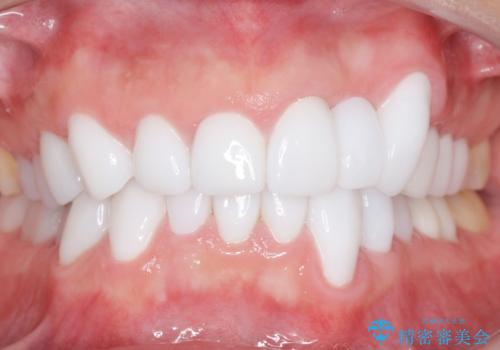

歯並びをきれいにしたい、歯を真っ白にしたい 40代男性

矯正治療とホワイトニングを提案しましたが希望されず、「接客関係の仕事で矯正治療は考えられない、短期間で治療を終わらせたい、ホワイトニングでは難しい位の人工的な白さにしたい」とのご要望により、治療前にワックスアップ模型を作製し何度もコンサルテーションを重ね、治療方針を決定しました。

歯頚ラインが変えられないことや天然歯を削るリスクをご理解頂いた上で、オールセラミッククラウンによる補綴治療を行いました。(見えない奥歯のみ天然歯のままとしました)

クラウンの色味・形態の修正や患者様のお仕事のご都合で来院できない期間があったことにより、予想より治療期間が長くなってしまいましたが、審美的な仕上がりにご満足頂けました。

クラウンの色味に関して、自然な白さ(シェードA1~NW0.5)のクラウンを作製・試適したところ「もっと白くしたい」と希望され、当院で最も明度の高い色(シェードNW0)に修正しました。

被せ物の種類:オールセラミッククラウン スタンダード (シェード:NW0)